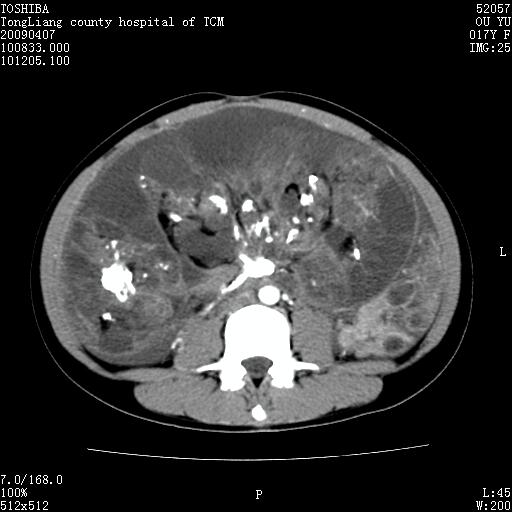

女,17岁,腹胀1月,b超示腹腔内巨大占位病变,腹水;

ct示腹腔内不均匀软组织肿块影,可见多数钙化灶(ct值400--800).周围肠管推移.

增强后,肿块内软组织不均匀强化,病灶内钙化灶边缘可见脂肪密度,肿块有包膜.向下与达盆腔.

腹部巨大紊杂密度肿块,边界不清楚,内有密度不均的软组织,多发不均匀钙化,钙化周围可见脂肪密度影,腹腔内可见积液及肿块内亦见液密密度区.增强后肿块内实质部分不均匀强化.钙化灶边缘脂肪灶显示更清楚.肠腔明显受推移.考虑畸恶性胎瘤.

增强后,肿块内软组织不均匀强化,病灶内钙化灶边缘可见脂肪密度,肿块有包膜.向下与达盆腔.[/quote]考虑畸胎瘤,恶性可能性大.